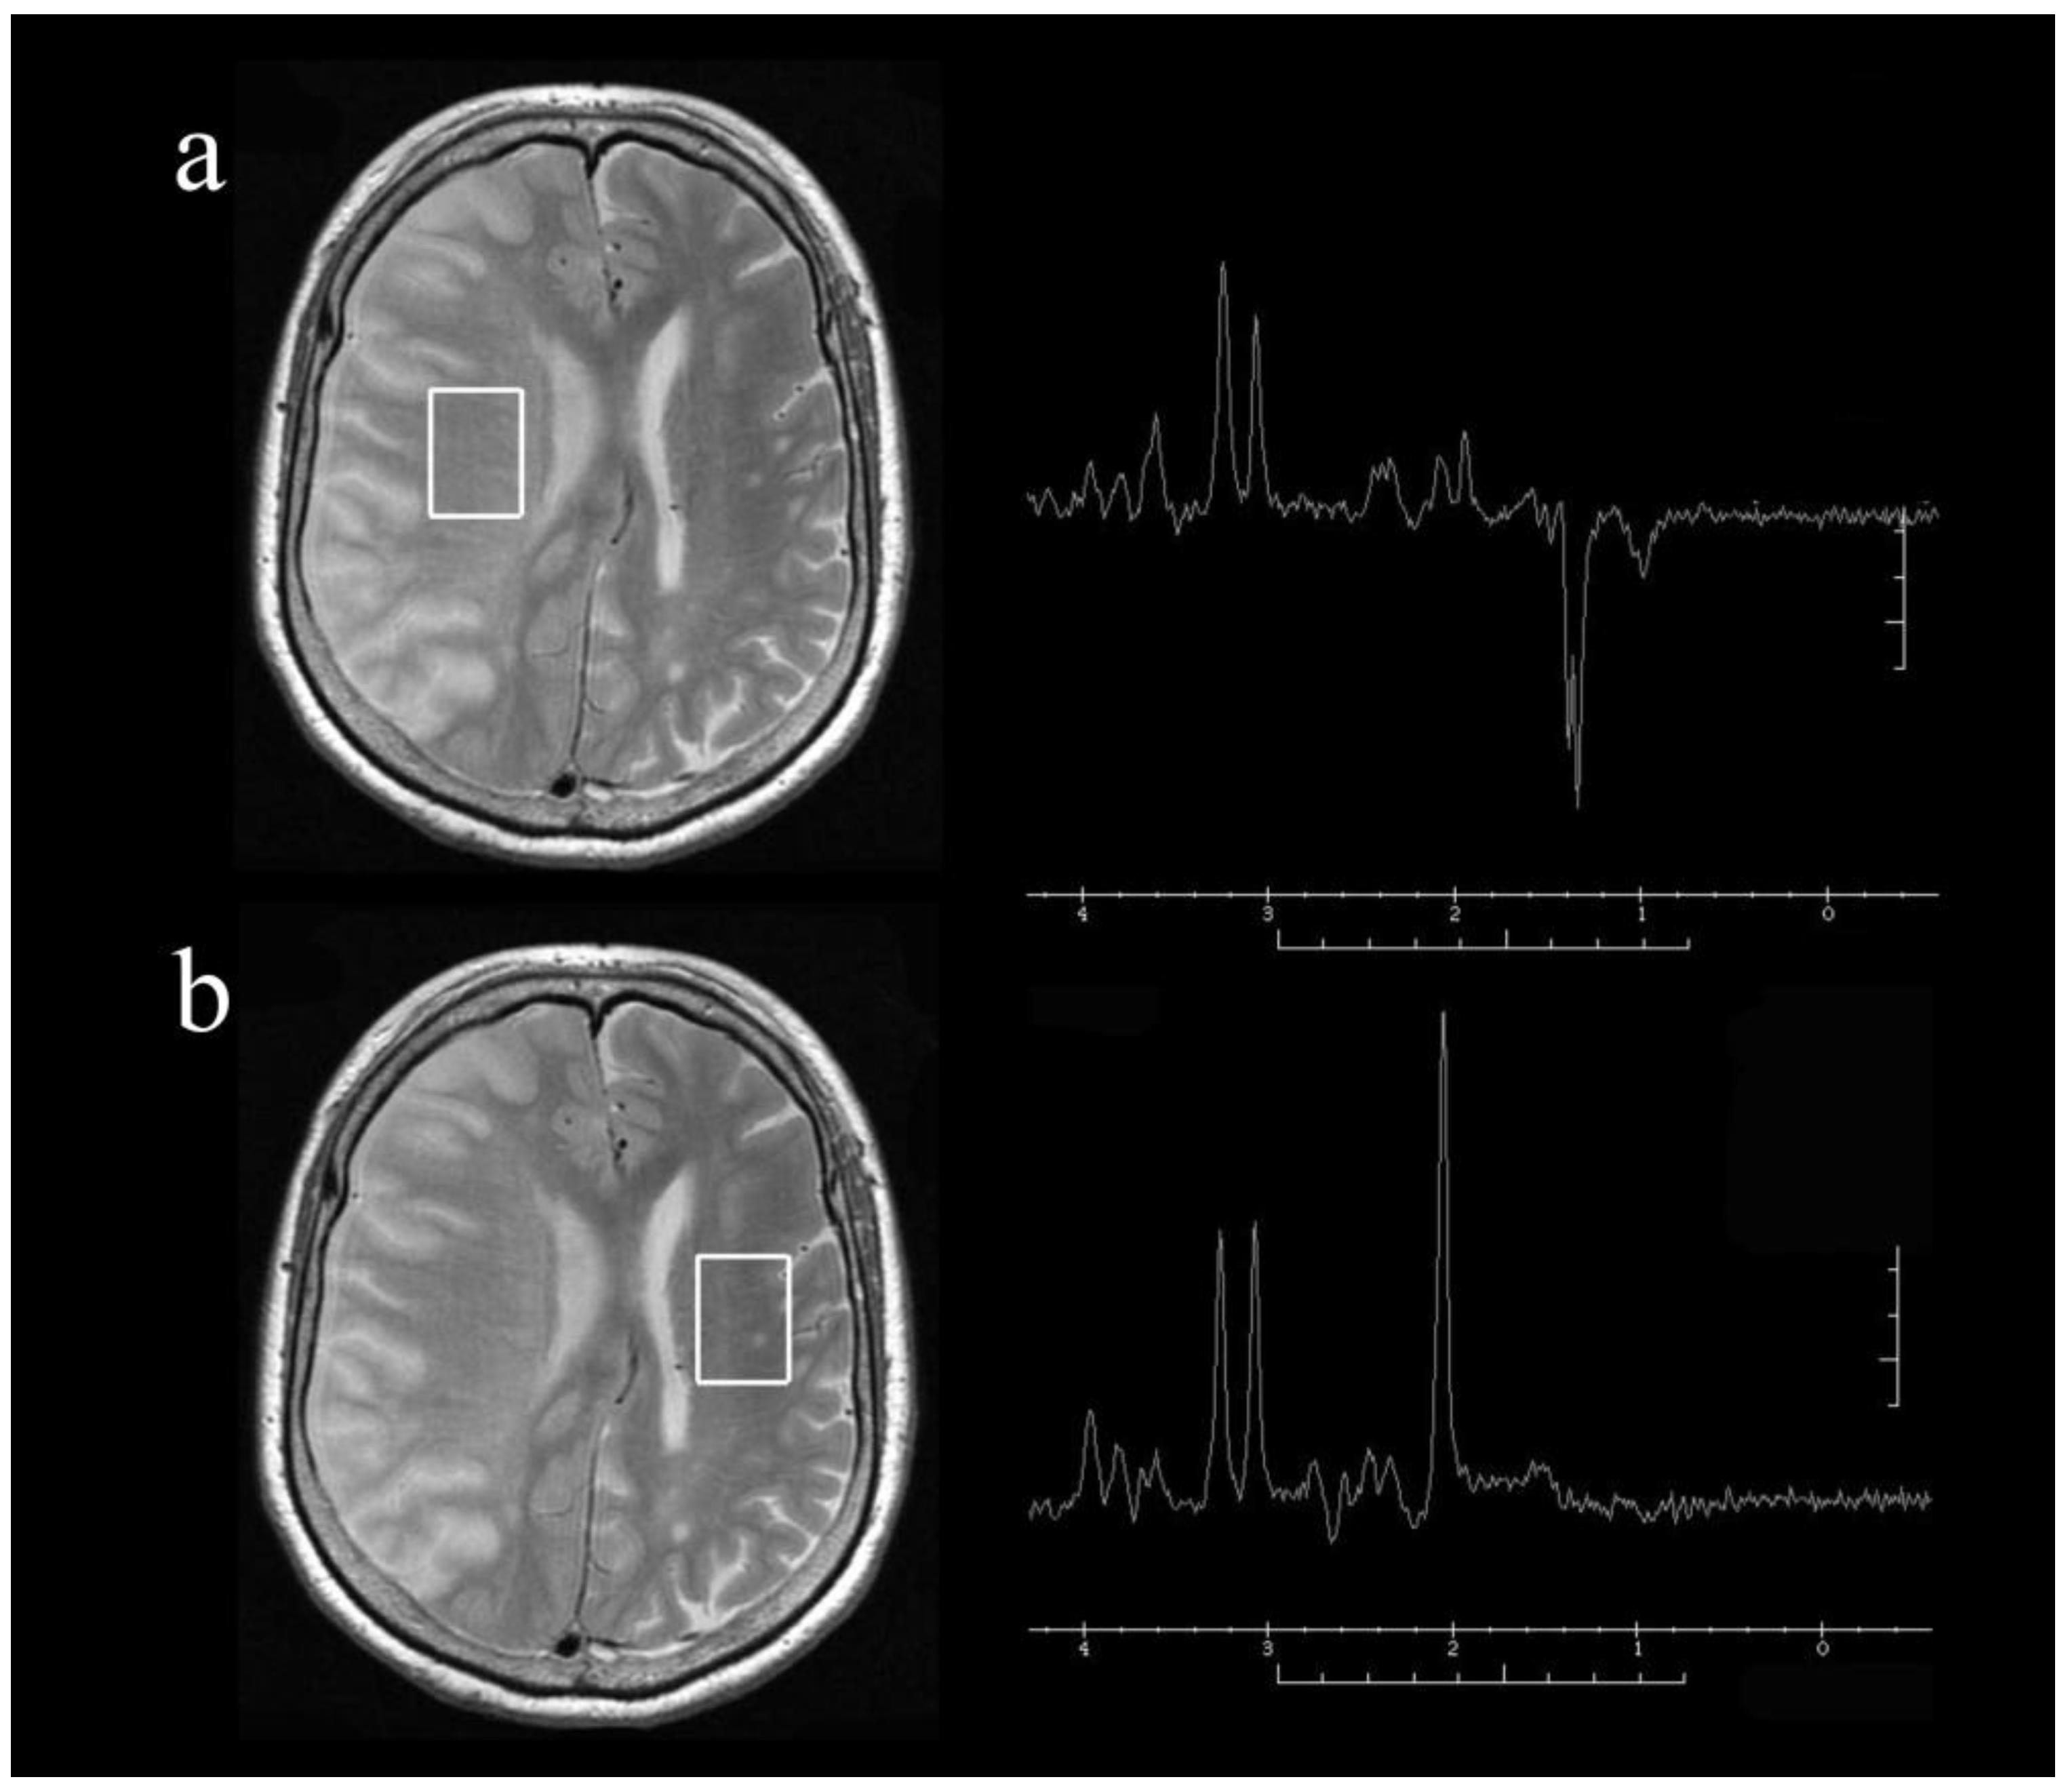

All MR imaging was performed using a Signa VH/i 3.0 T MR imaging system (General Electric Medical Systems, Milwaukee, WI, USA) and parallel imaging head coil. Imaging with a 3.0 T system has been previously reported to give good accuracy [27,28]. For T2-weighted MR imaging, the short inversion time inversion recovery sequence was used with the following parameters: repetition time (TR), 4000 ms; echo time (TE), 81 ms; inversion time, 100 ms; matrix, 512 × 384; field of view, 400 mm; and 3.5-mm slice thickness. Single-voxel MR spectroscopy was performed with the following parameters: TR 2000 ms, TE 144 ms, and 128 excitations. A point-resolved spectroscopy pulse sequence was used. The voxels of interest, with a size of 20 mm × 20 mm × 30 mm, were set in the infarct area and the contralateral area of each patient, as identified on T2-weighted images (Figure 1). The image acquisition took 15 min (not including patient settling time), and the environmental temperature was maintained at 21 °C to 25 °C. The MR spectra included peaks assigned to choline-containing compounds at 3.2 parts per million (ppm), creatine phosphate at 3.0 ppm, and NAA at 2.0 ppm. All spectra were inspected visually and discarded if judged to be of poor quality (i.e., if the signal-to-noise ratio was such that peaks were unable to be detected). Brain temperature was calculated from the chemical shift between water and choline-containing compounds, creatine phosphate, or NAA; the most recognizable of the three peaks was used for each measurement. To calculate the brain temperature, a 0.01 ppm shift in the water peak was taken as a 1 °C change [6,9,29]. The ratio of brain temperature in the affected hemisphere to that in the contralateral hemisphere was then calculated for each patient, as reported previously [6,9].

Figure 1. Representative axial T2-weighted magnetic resonance images and single-voxel proton magnetic resonance spectra obtained from the voxels of interest (square areas) in the infarct hemisphere (a) and normal hemisphere (b) of a patient with right internal carotid artery occlusion at 24 h after onset. Note the presence of lactate with relatively preserved N-acetyl aspartate (NAA) in the infarct hemisphere.